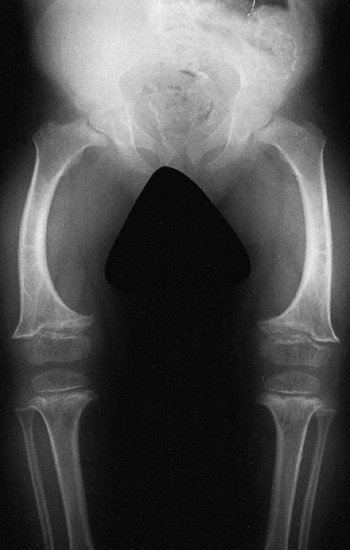

![]() |

Figure 8.2 A 16-year-old boy with achondroplasia. A: Pronounced shortening of proximal limb segments (rhizomelic pattern). There is mild genu varum. The humeri are most affected. B: The elbows have a mild flexion contracture. He has had previous osteotomies of the tibias and fibulas for varus.